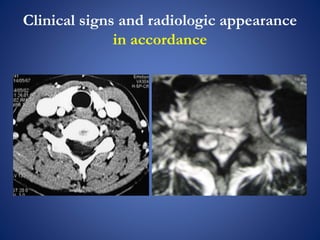

Clinical signs and radiologic appearance

in accordance

Clinical signs andradiologic appearance in accordance